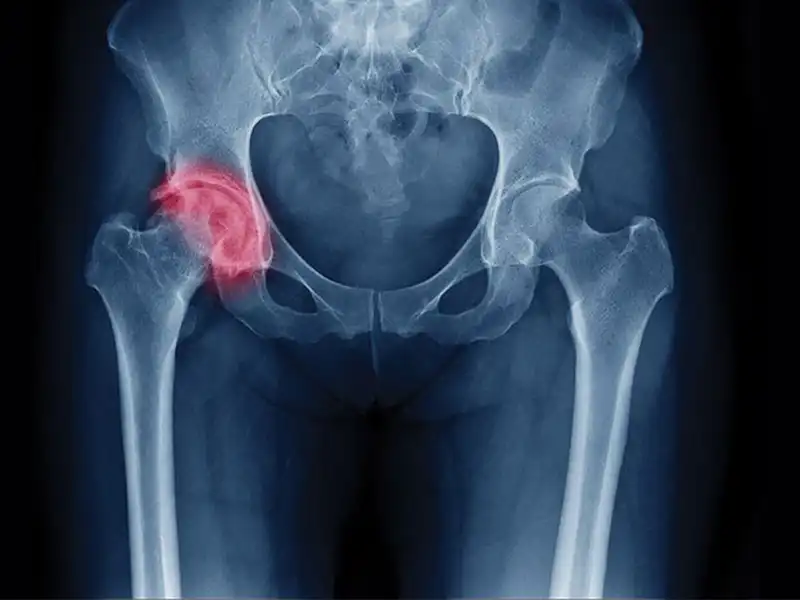

مشهد به عنوان یکی از کلانشهرهای ایران، میزبان جراحان ارتوپدی متخصص و فوق تخصص در زمینه جراحی لگن است. این جراحان با بهره ‌گیری از پیشرفته ‌ترین تکنیک‌ های جراحی و تجهیزات مدرن پزشکی، خدمات تخصصی در زمینه ‌های مختلف از جمله تعویض مفصل لگن، درمان شکستگی ‌های پیچیده و جراحی‌ های بازسازی لگن ارائه می ‌دهند.

دکتر افشاریان دارای برد تخصصی ارتوپدی و فلوشیپ جراحی لگن و مفصل ران از دانشگاه‌ های معتبر ایران هستند. ایشان با بهره‌ گیری از جدیدترین تکنیک ‌های جراحی، موفقیت ‌های چشمگیری در زمینه ‌های مختلف جراحی لگن داشته‌ اند. از جمله این روش ‌ها می‌توان به جراحی تعویض کامل مفصل لگن، جراحی ‌های بازسازی لگن، درمان شکستگی ‌های پیچیده ناحیه لگن و تصحیح دفورمیتی‌ های این ناحیه اشاره کرد.